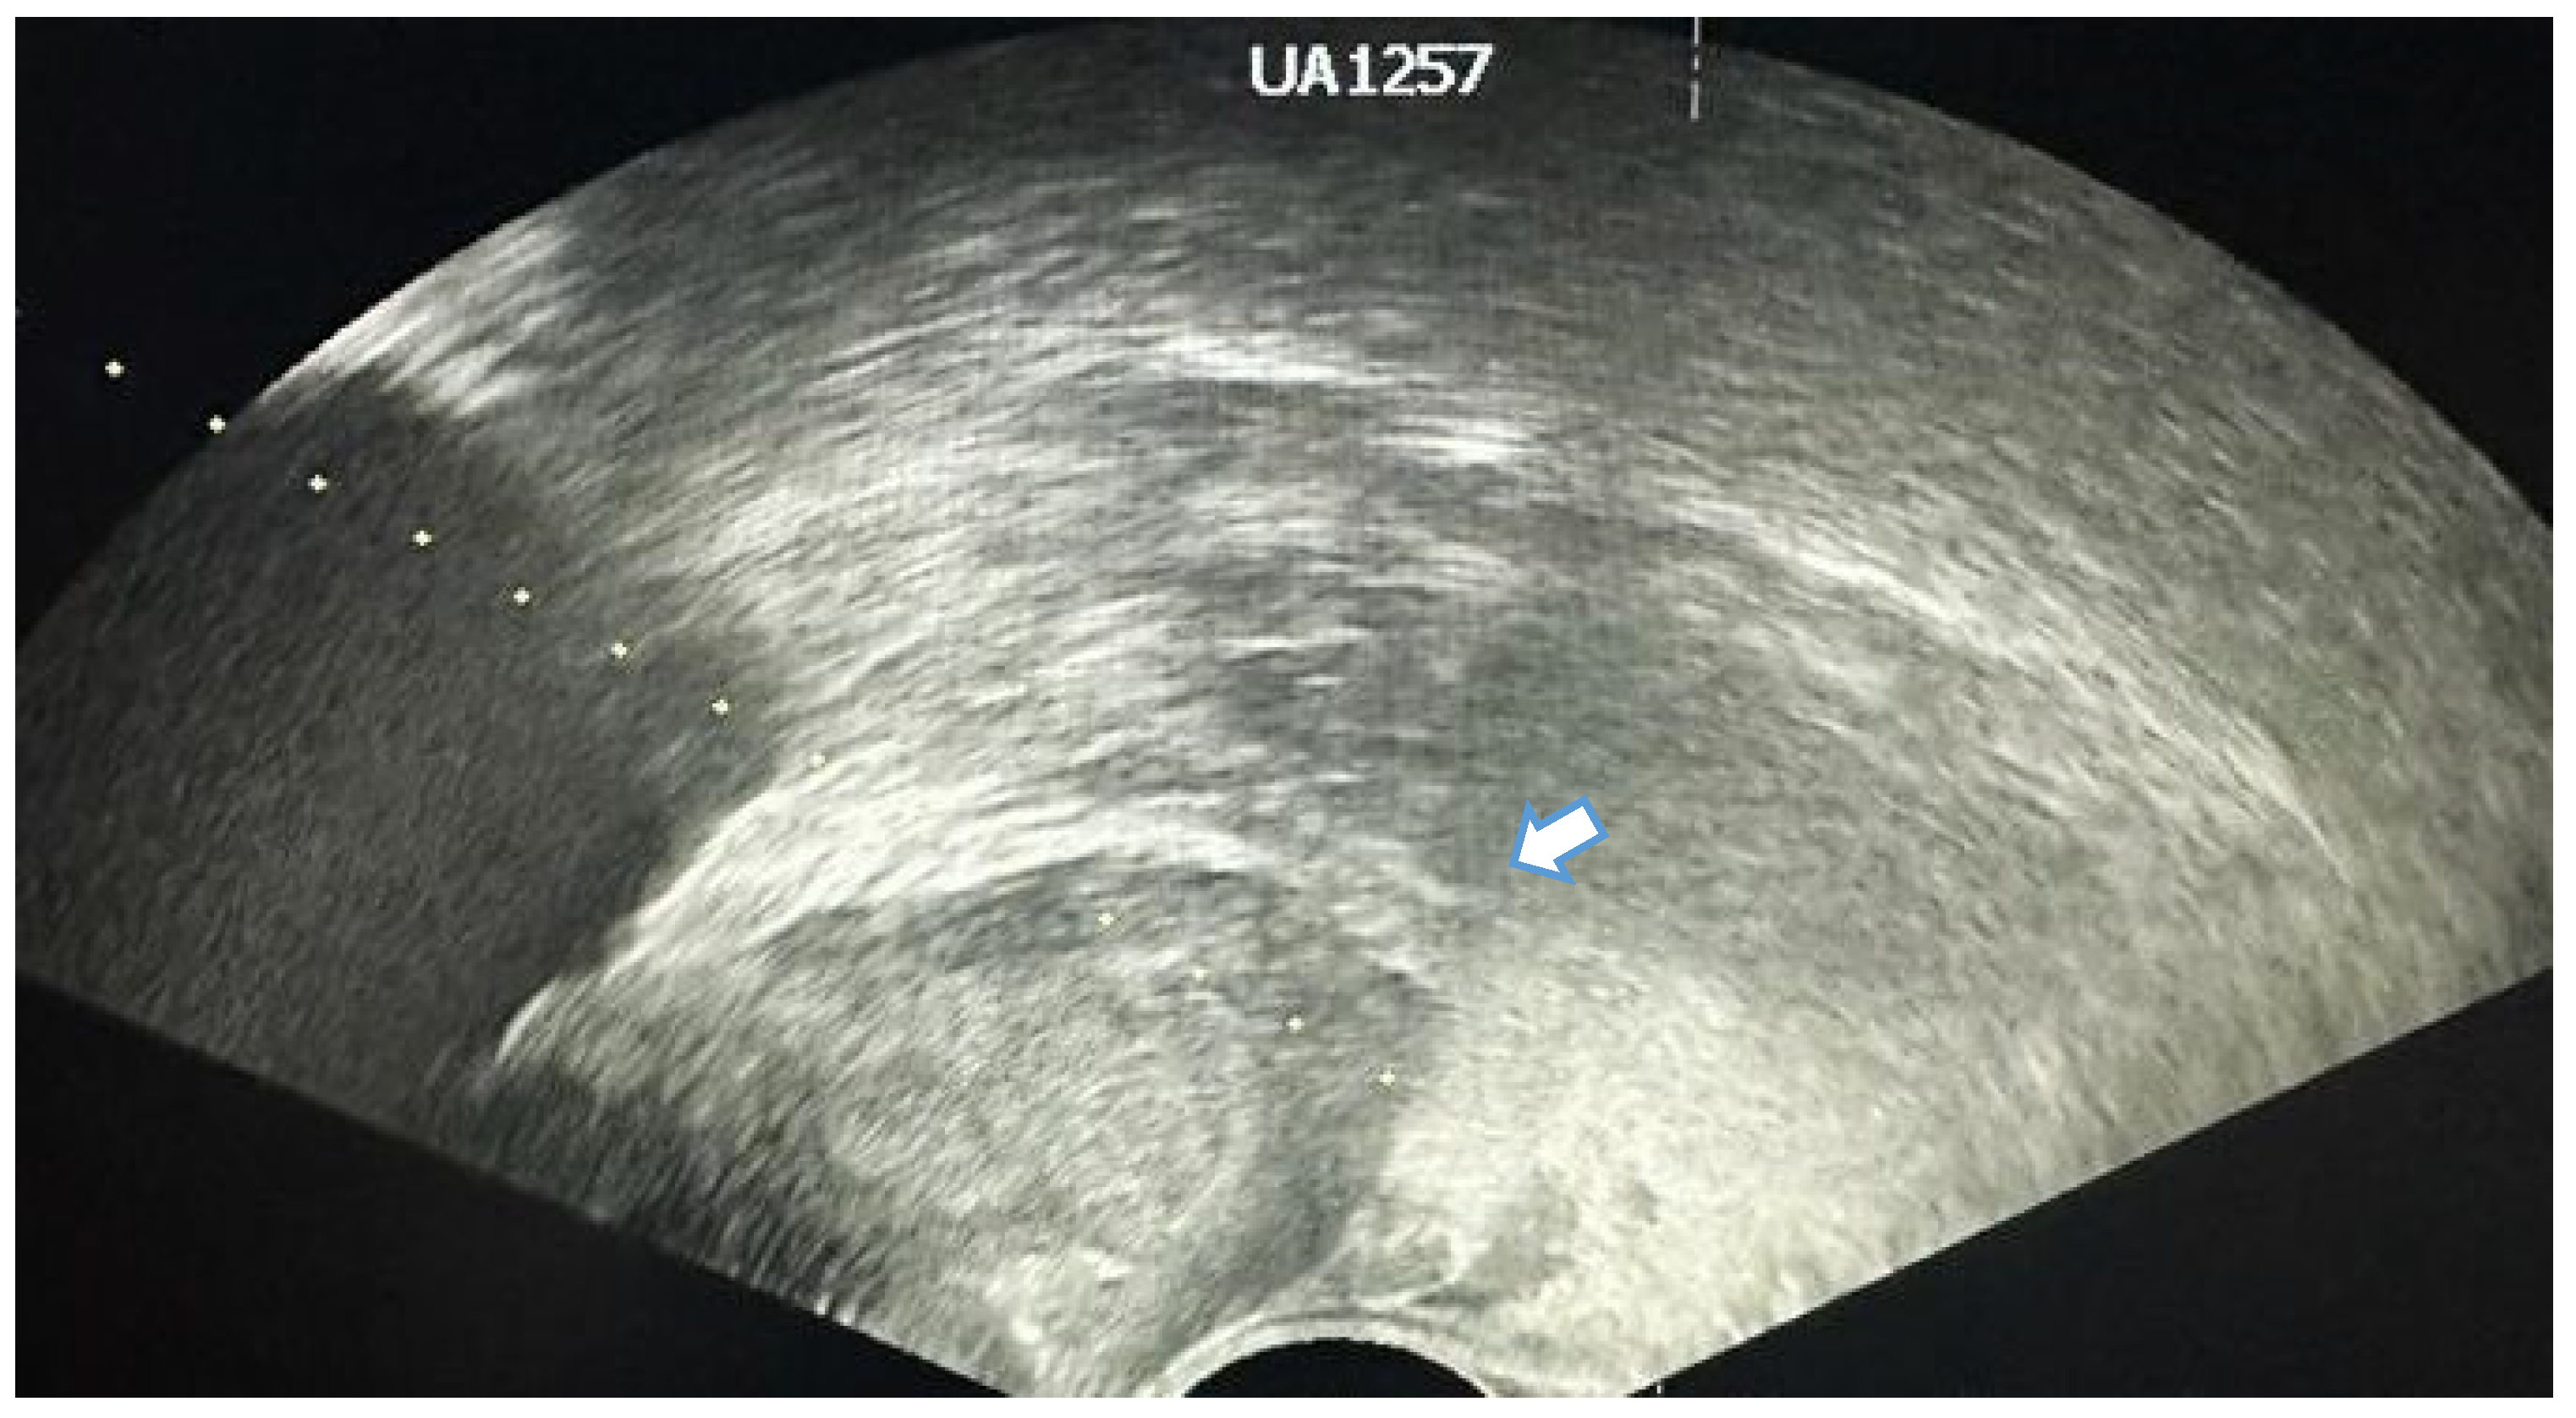

4. Transrectal Ultrasound (TRUS)-Guided Prostate Biopsy

6. Technical Difficulties

6.4. Location of the Suspicious Lesion